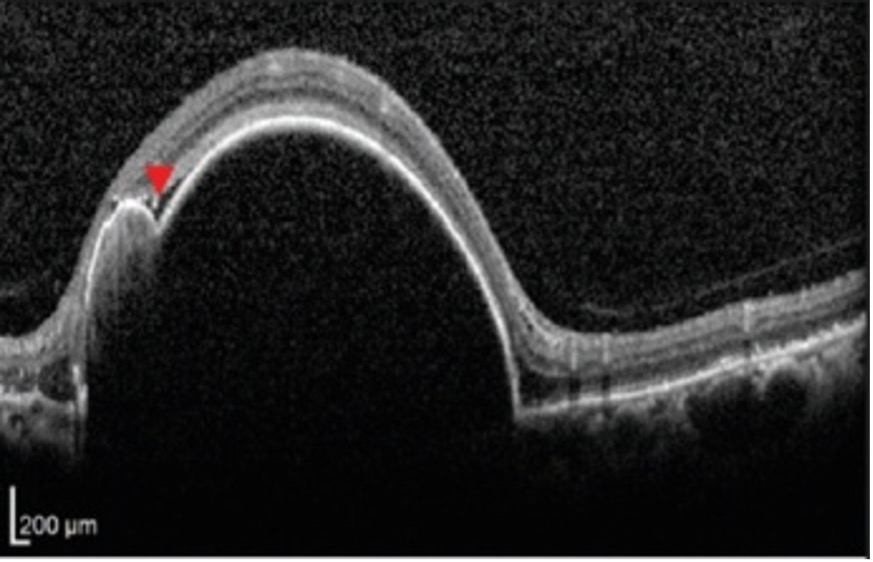

Let’s read and interpret this last OCT scan.

Here there is a gross elevation of RPE (hyper-reflective line bordering retina and choroid). And also note there is an irregularity in RPE elevation with a second bump (a notch) marked by an arrowhead. This tells us that the basic pathology is located below the retina viz choroid and by correlating this OCT image with the clinical fundus we interpret this huge bump to a notched ped and so we derive a differential diagnosis of PCV.